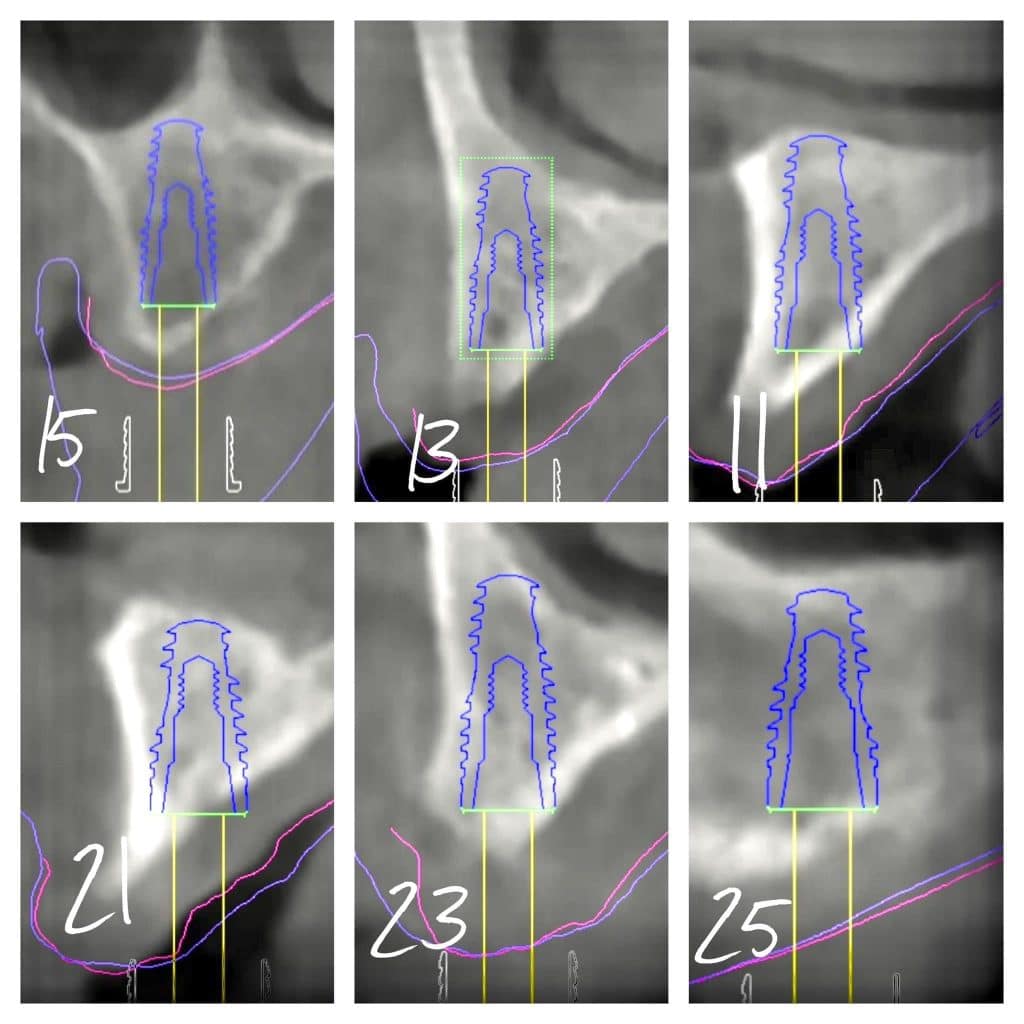

here a case where a full mouth réhabilitation was done by placing 6 implants

multiunit abutement were placed and a temporary bridge also was made for emergence profile shaping